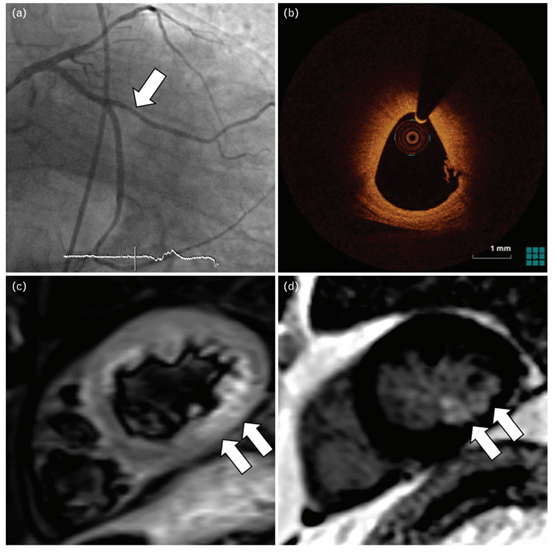

冠状动脉血栓形成患者的影像学检查

(a)冠状动脉造影显示非ST段心肌梗死患者的大钝缘支轻度病变(箭头); (b)光学相干断层扫描显示血栓覆盖纤维斑块; (c)心脏磁共振成像

共振显示对应于心肌水肿

的T2高信号(↖)以及(d)下侧壁心内膜下晚期钆增强(↖)